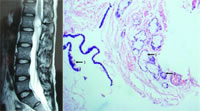

磁共振成像(MRI)检查发现,患者腰1椎体水平(第一腰椎椎管内)可见约2.0 cm×1.7 cm×1.5 cm大小卵圆形异常信号(图1)。术后病理诊断结果为椎管内支气管源性囊肿(图2)。随访一年,患者恢复良好,未复发。

图1 MRI检查结果

图2 病理检查结果(放大200倍)

黏膜下有浆液腺(箭头1)、黏液腺(箭头2)等成份,箭头3指示结缔组织性囊壁,内衬假复层纤毛柱状上皮。, http://www.100md.com